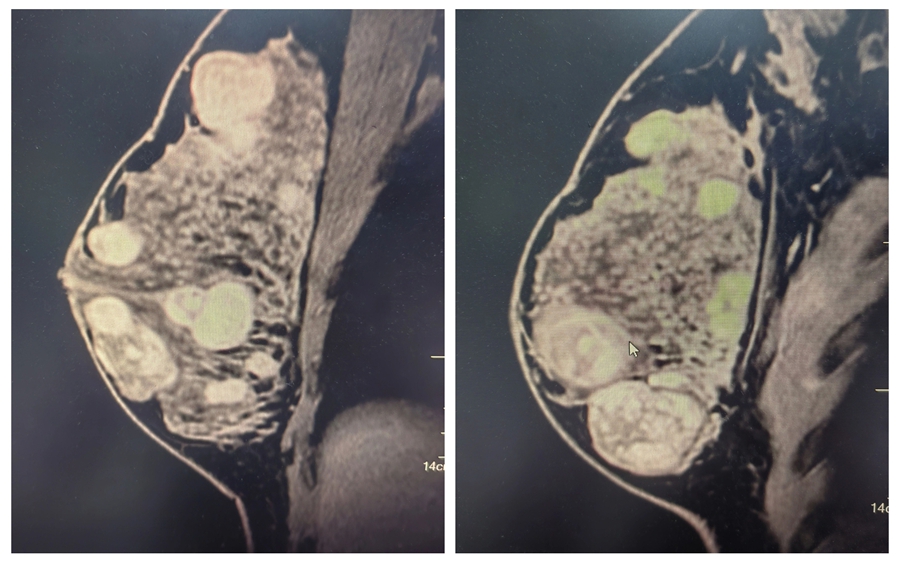

患者晓莉(化名)因自觉双侧乳房“疙疙瘩瘩”前来就诊,乳腺超声检查令人心头一紧,双侧乳房都长了结节,右侧乳腺更多,部分小结节融合成大结节,最大的直径达 5 厘米。

△乳腺核磁共振检查可见多结节分布